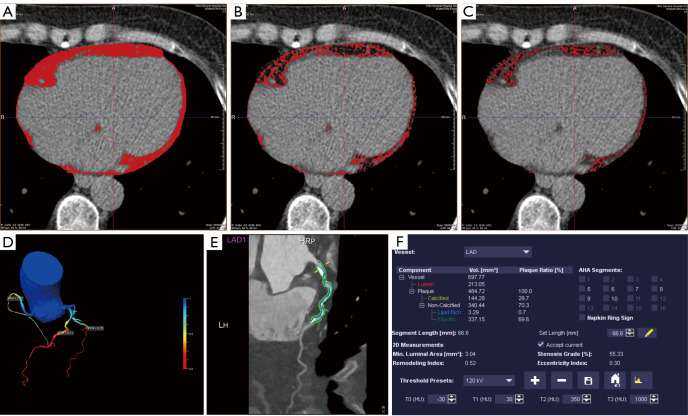

Methods: The clinical risk factors and imaging images of 107 CAD patients were retrospectively analyzed. Quantification of coronary artery calcium scores (CACS), PF, WAT, BAT, and pericardial fat attenuation (PFatt) were performed on non-contrast CT images. CCTA was used to evaluate myocardial ischemia and the presence of HRP. Fractional flow reserve derived from CCTA (CT-FFR) was performed in three major coronary arteries, with a threshold of ≤0.80 considered indicative of the presence of lesion-specific ischemia. HRP was defined as the presence of at least two of the four HRP features including positive remodeling (PR), low attenuation, napkin-ring sign (NRS), and spotty calcification. Mediator analysis was performed using Hayes (2018) Model-4.

Results: A total of 107 CAD patients aged 65±8 years were included in this study. There were 49 patients (45.79%) with HRP and 57 patients (53.27%) with lesion-specific ischemia (CT-FFR ≤0.80). PF including WAT and BAT in the HRP group was significantly higher than that in the non-HRP group (PF: 241.28 vs. 204.94 cm3, P=0.005, WAT: 91.78 vs. 78.40 cm3, P=0.002, BAT: 56.25 vs. 46.71 cm3, P=0.008). Adding WAT to meaningful clinical risk factors and CACS increases the area under the curve (AUC) for HRP prediction {AUC [95% confidence interval (95% CI)]: 0.789 (0.692-0.887) vs. 0.655 (0.535-0.775), P<0.05}. Interestingly, adding PF to clinical risk factors and CACS decreased the AUC for the prediction of lesion-specific ischemia with no significant difference (P=0.083) [AUC (95% CI): 0.705 (0.592-0.817) vs. 0.796 (0.696-0.897), P<0.05]. Additionally, the mediation effect of PF accounted for 95.19% of the total effect of clinical risk factors on HRP (P<0.05).

Conclusions: PF is associated with HRP, and clinical risk factors increase the risk of plaque rupture by promoting PF volume accumulation, especially WAT, which may be a potential predictor of HRP.